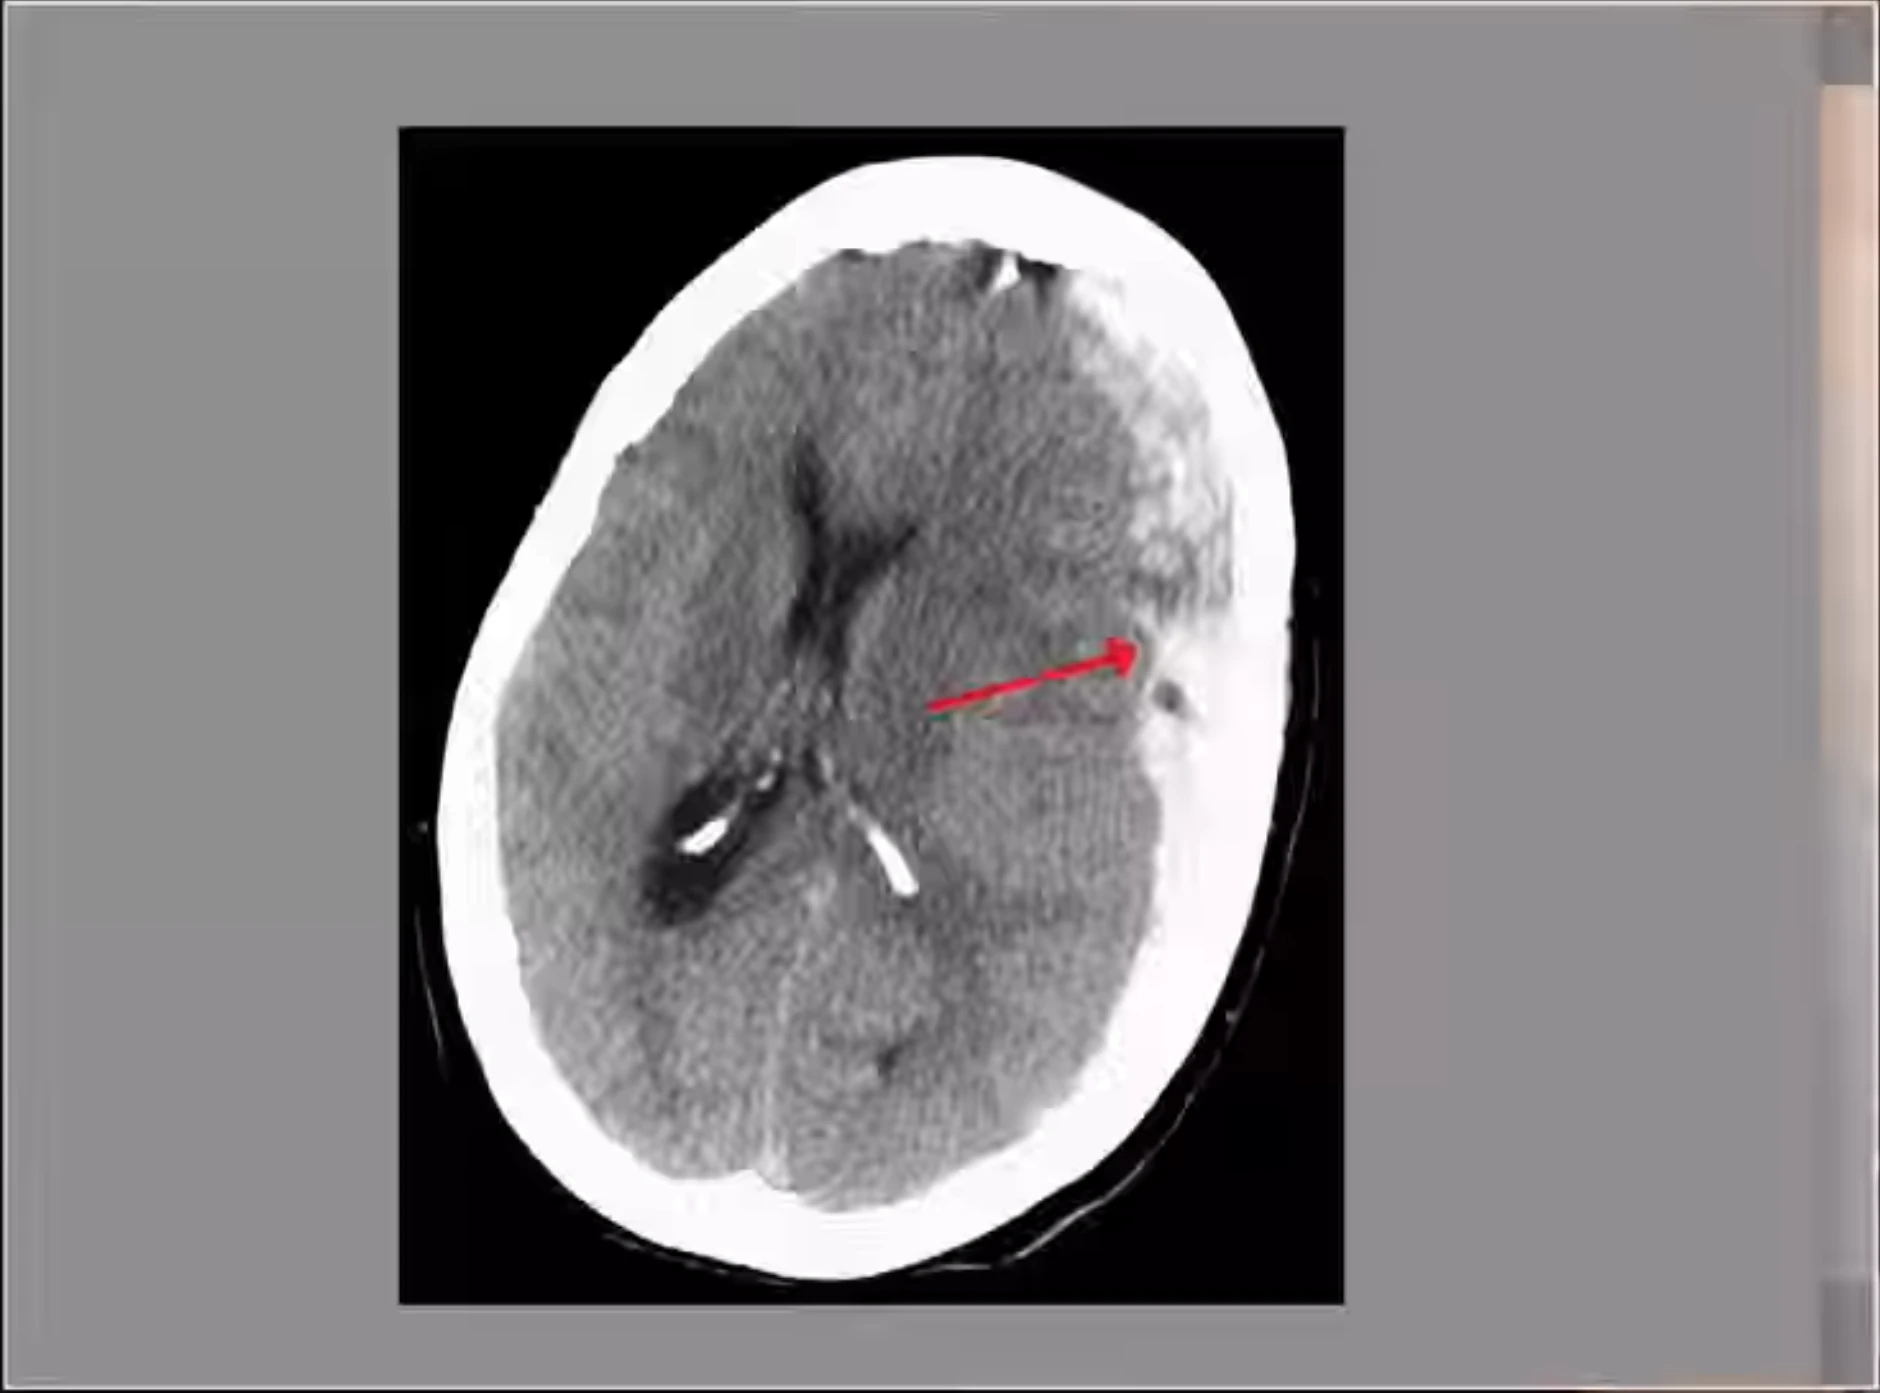

Shigetoshi Kotari and Hiromasa Urakawa have died after boxers fight due to brain injuries caused by hits during a fight which eventually lead to internal bleeding and generating a pressure on brain by a accumulated blood between skull and tissue's, above brain tissue's. Shigetoshi Kotari has died on Friday - 08.08.2025 and Hiromasa Urakawa has died on Saturday 09.08.2025. Kotari has died after fight with Yamato Hata. Urakawa has died after fight with Yoji Saito.

Shigetoshi Kotari and Hiromasa Urakawa have died after boxers fight due to brain injuries caused by hits during a fight which eventually lead to internal bleeding and generating a pressure on brain by a accumulated blood between skull and tissue's, above brain tissue's. Shigetoshi Kotari has died on Friday - 08.08.2025 and Hiromasa Urakawa has died on Saturday 09.08.2025. Kotari has died after fight with Yamato Hata. Urakawa has died after fight with Yoji Saito. Video attached is a medical analysis of death causes both boxers.